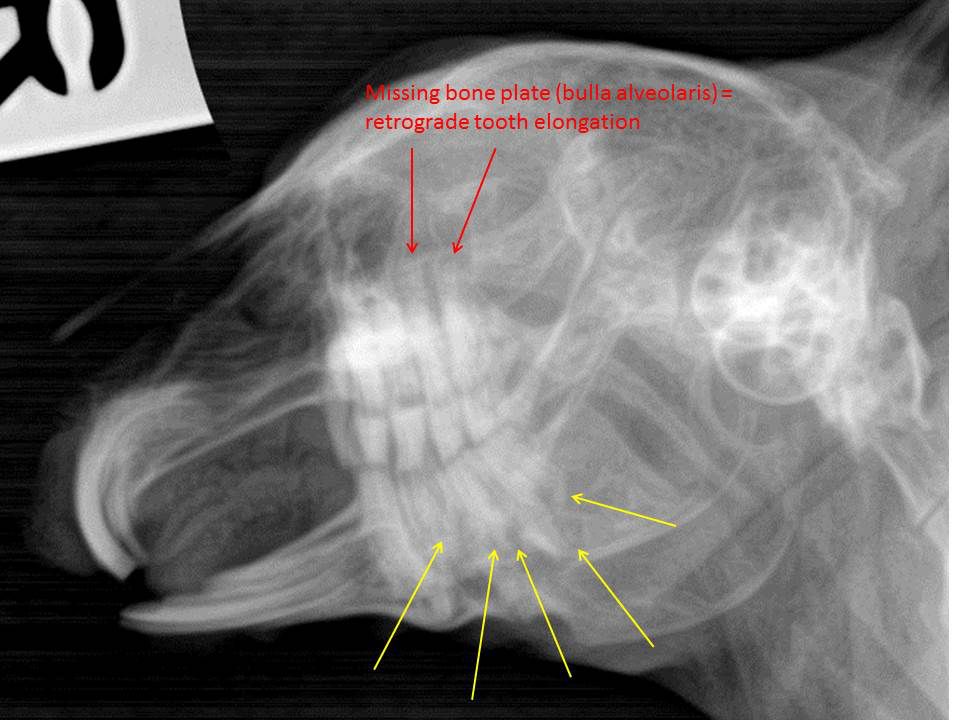

Thank you for posting the images and the rads. This rabbit has indeed a cheek tooth malocclusion – as you mentioned above. And therefore this is a secondary = acquired incisor malocclusion. The main problem are the cheek teeth and an extraction of all incisors would not „help“ this animal – it’s contraindicated, in my opinion. I tried to mark some pathological findings that need further diagnostic work-up (but unfortunately your rads are very blurry on my screen) and – if possible – more targeted therapy. Only trimming the theeth on a regular basis does not seem to be enough for this poor guy. The rabbit suffers from an advanced enamel-and dentin hypoplasia (almost all cheek teeth show an abnormal dental structure that should be visible on intraoral exam as well = pathological appearance of the occlusal plane). In addition to that, multiple teeth have signs of intradental lysis. If it’s real caries or FORL-like tooth resorption cannot be assessed based on these radiographs. You need a full set of skull-rads (four views: latero-lateral for using the reference lines, dv (neck pressed down to the table), both sides oblique (head tilted about 40 degrees) and if feasible intraoral rads. Alternatively a CT study can be recommended (this depends on the owner – costs).